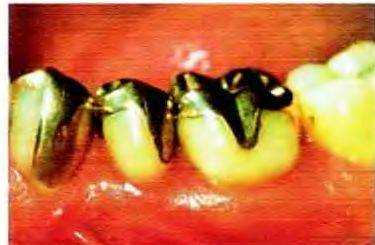

Fmc 12-54. Для восстановления моляра было решено использовать МОД-накладку, поскольку кариозная полость в центре зуба ослабила его грочностъ. На проксимальных поверхностях обнаружено несколько мелких трещин.

Рис. 12-57. Окклюзионный вид не леченного премоляра верхней челюсти Небольшая кариозная полость на дистальной поверхности и трещина на медиальном краевом гребне. Зуб чувствителен к температурным раздражителям и к вертикальному давлению, однако бессимптомен при перкуссии